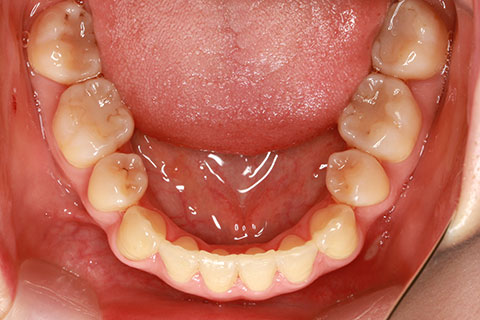

治療前

治療中(開始直後)

治療中(開始半年後)

治療後

- 年齢・性別

- 25歳女性

- 治療期間

- 2年0ヶ月

- 抜歯

- 上下4番抜歯

- 治療費

- 110万円

- 治療内容

- 施術の副作用(リスク)

- 表側矯正と比較して、力学的な操作性が複雑なため、ボーイングエフェクトを起こしやすい。